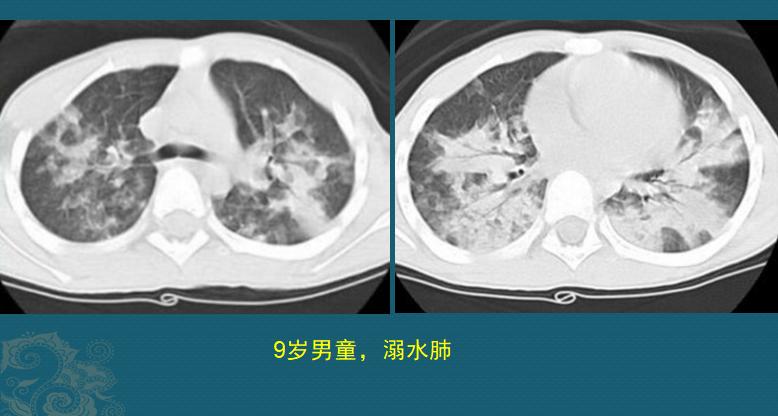

下图是鹤壁市人民医院汪涛医生分享的病例,是一位9岁小男孩,溺水后发生了肺水肿,合并弥漫性肺泡损伤,呈白色的多发肺实变,沿气道分布,好在最终也抢救成功,比上面那位女士好得慢一点: